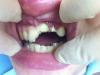

Dr.Sapronov Опубликовано 7 марта, 2013 Автор Поделиться Опубликовано 7 марта, 2013 С каппой наврятли получится, т.к. Там клиника достаточно слабовата по снабжению. Но все самое необходимое есть . Прикрепил фото, к сожалению у меня только одна фотография, где пациентка после пломбирования к/к. Постараюсь в четверг сфоткать. До и с лоскутом. Ссылка на комментарий

Dr.Sapronov Опубликовано 14 марта, 2013 Автор Поделиться Опубликовано 14 марта, 2013 (изменено) Вот и пришла ко мне девушка - выкладываю фото. Циркониевые вкладки о которых писал выше. Взял трансплантат с неба и пришил в области рецессии. Хочу услышать ваше мнение и критику. Фотографировал на телефон. Работа эта у меня первая такого рода, до Стаси далеко конечно, но надо с чего-то начинать. Сверху положил диплен плёнку (зачем не знаю, подумал, что так будет лучше.) в итоге немного покровило и кадр испортился. Через 10 дней сфоткаю еще раз когда буду снимать швы. Изменено 14 марта, 2013 пользователем Dr.Sapronov Ссылка на комментарий

DShu Опубликовано 15 марта, 2013 Поделиться Опубликовано 15 марта, 2013 Вот и пришла ко мне девушка - выкладываю фото. Циркониевые вкладки о которых писал выше. Взял трансплантат с неба и пришил в области рецессии. Хочу услышать ваше мнение и критику. Фотографировал на телефон. Работа эта у меня первая такого рода, до Стаси далеко конечно, но надо с чего-то начинать. Сверху положил диплен плёнку (зачем не знаю, подумал, что так будет лучше.) в итоге немного покровило и кадр испортился.Док, уж лучше вообще не фоткать, чем так. Смотреть невозможно! Каша какая то. Ссылка на комментарий

pit Опубликовано 15 марта, 2013 Поделиться Опубликовано 15 марта, 2013 Вот и пришла ко мне девушка - выкладываю фото. Циркониевые вкладки о которых писал выше. ........ Хочу услышать ваше мнение и критику. Фотографировал на телефон..................... в итоге немного покровило и кадр испортился. По фото ничего не понятно, действительно, видимо кадр испортился.Вся критика направлена на качество фото, потому что ничего не видно!!!!Обязательно выложите фото через 10 дней, только в хорошем качестве. Ссылка на комментарий